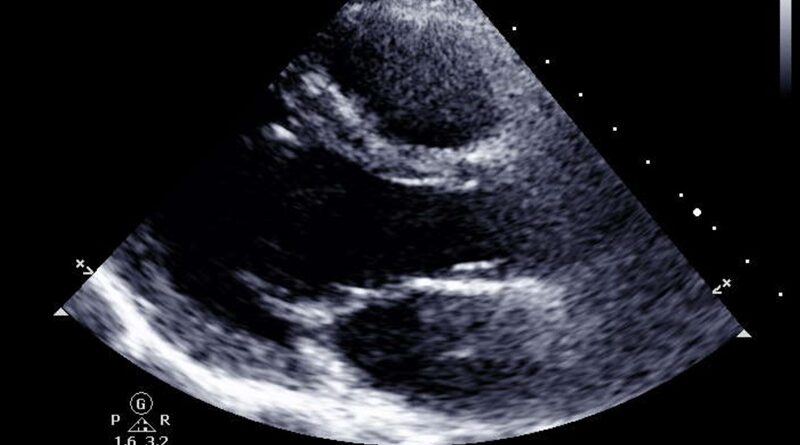

A 2D Heart Scan is a diagnostic test that allows an ultrasound specialist to check your heart’s health and structure. It provides detailed images of the heart and its chambers, valves, and other structures. This scan is also referred to as an echocardiogram. ultrasound specialist will use high-frequency sound waves to create images of the heart and assess its function. The images will help them determine the size, shape, and functioning of the heart. The scan can also reveal any issues with the heart’s walls, valves, or blood vessels.

A 2D heart scan from an ultrasound specialist can provide you with peace of mind by helping to detect any issues or abnormalities in the structure of your heart. It is a type of medical imaging that uses sound waves to create images of the heart. With this, a trained ultrasound specialist can evaluate the size, shape, and functioning of the heart and its components. This can be done to diagnose conditions such as a heart attack, an arrhythmia, a valve disorder, an enlarged heart, or a congenital defect.

A 2D heart scan is a non-invasive ultrasound procedure that provides detailed images of the heart and surrounding structures. During the procedure, an ultrasound specialist will apply a special gel to the patient’s chest to help transmit the sound waves from the transducer (or ultrasound probe) to the patient’s body. These images also provide valuable information about any potential medical issues that could affect the heart, such as blockages or valve abnormalities. After capturing these images, the ultrasound specialist can then discuss their findings with the patient and recommend any necessary treatments.